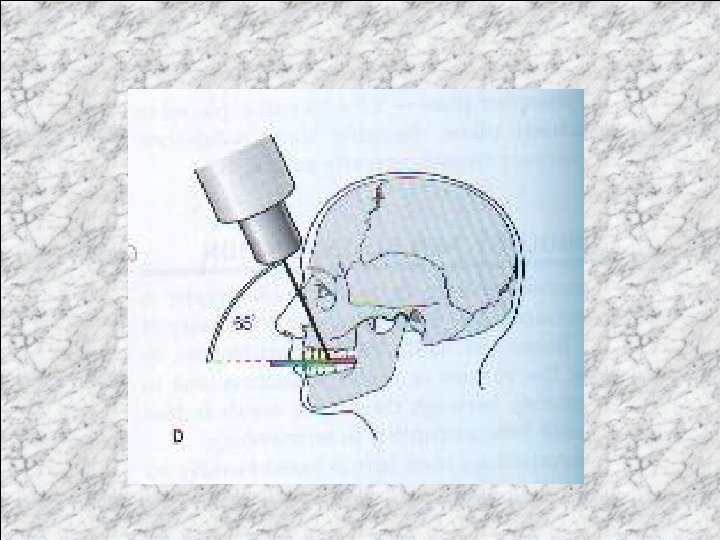

Lower 45 o (anterior) occlusal The patient is seated with the head supported and with the occlusal plane horizontal and parallel to the floor. The image receptor facing downwards is placed centrally into the mouth, on the occlusal surface of the lower teeth, with long axis anteroposeriorly. The patient is asked to bite together gently. The X-ray tubehead is position in the midline centering through the chin point at angle of 45 o to the image receptor.